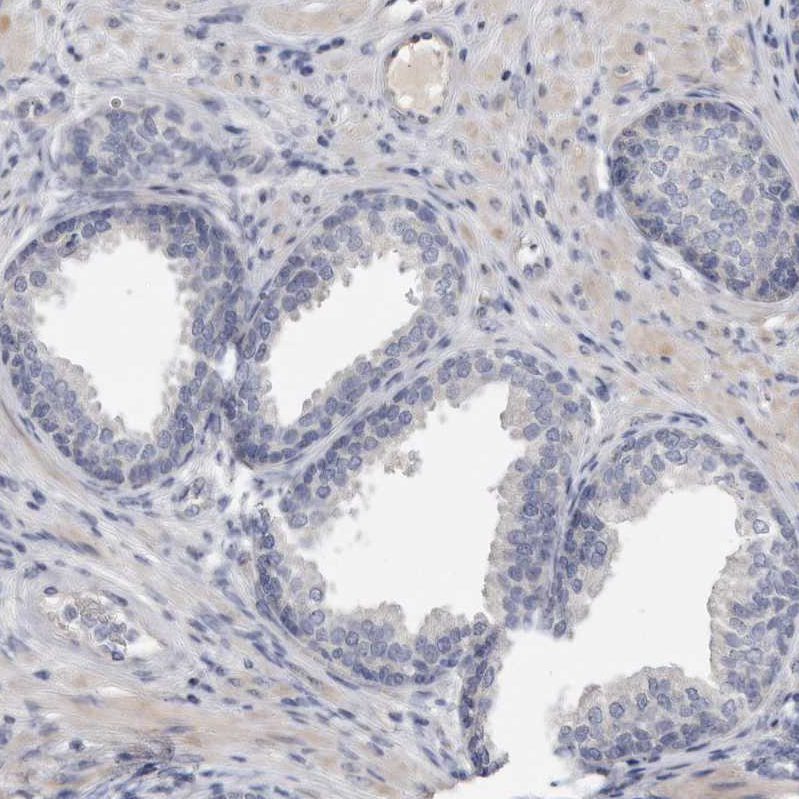

Immunohistochemical staining of human bone marrow shows moderate membranous positivity in hematopoietic cells.